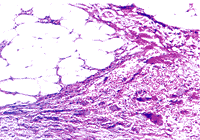

合併急性胰腺炎不同程度的水腫、出血和壞死是急性胰腺炎的基本病理改變,根據病變程度的輕重不同,胰腺炎分成急性水腫性胰腺炎和急性出血壞死性胰腺炎兩類。